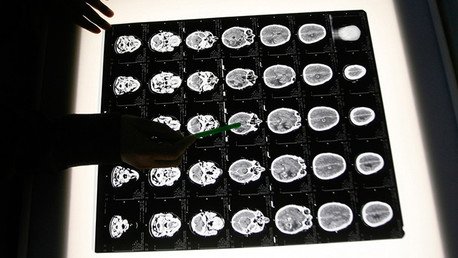

Carrasco y su grupo de investigadores, mediante el análisis 25 muestras de tejido cerebral de cadáveres, prueba que la presencia de proteínas fúngicas en las neuronas y en diversas zonas del cerebro en aquellos afectados por la enfermedad (14 pacientes), mientras que no fue detectada ninguna infección de este tipo en aquellos que no la padecían (11 pacientes).